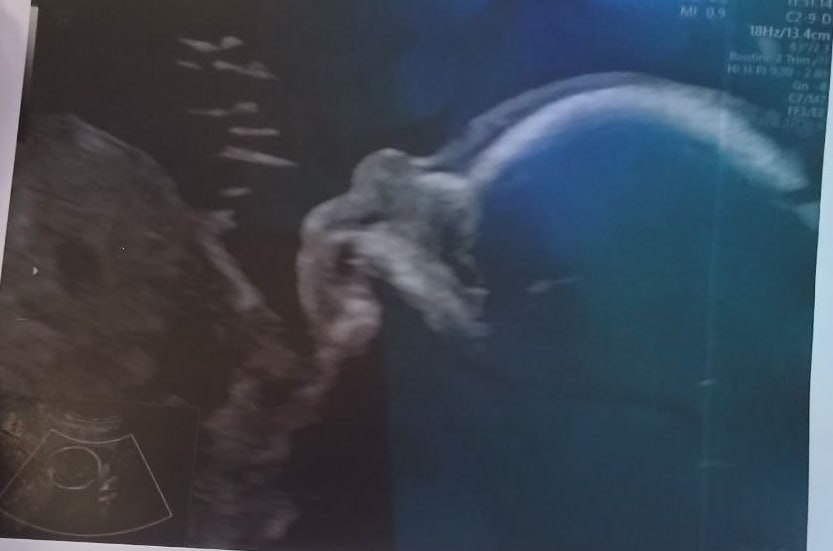

"Вчера все точно подтвердили, что будет сын. Я даже прослезилась. Я изначально знала. Впервые в жизни я поняла, что готова вырастить мужчину, хотя зарекалась, что сына никогда [не хотела] и вообще мне только Евы достаточно, о дочери я всю жизнь мечтала", — пишет Скворцова.